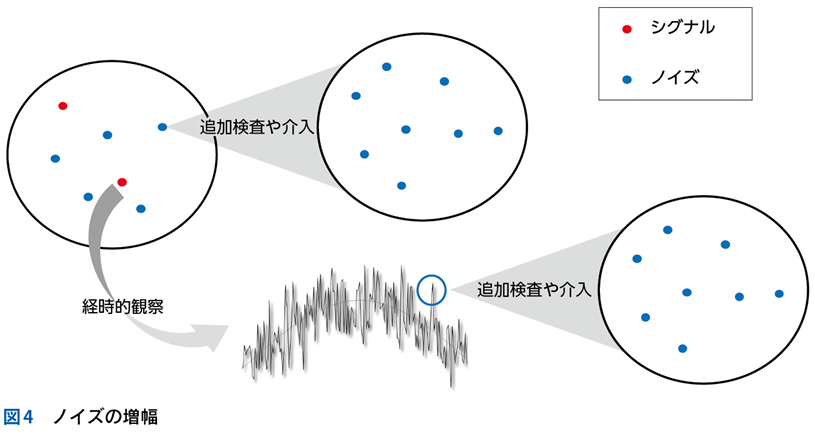

5 ノイズと多元論

▶ 「ノイズ」は,筆者的には臨床推論においてきわめて重要な概念であるため,第4章で詳述するが,フレーミングに関わるのでここで簡単に紹介しよう。ここでは「ノイズ」を,「患者の持つ情報のうち診断と直接的には関連しないもの」を指す語として使用する。対義語(診断と関連する情報)は「シグナル」である。星座のたとえで言えば「シグナル」は星座を構成する星,「ノイズ」は星座を構成しないが近傍にある「くず星」を指す(図4)。

▶ くず星とひとまとめに呼んでしまったが,厳密に言えばノイズには質的に「偽陽性情報」と「多元論で説明される情報」の2種類がある。前者は器質的疾患のシグナルではない情報であり,診断と無関係な疫学的情報,器質因のない症状,検査データのランダムなゆらぎといった,純粋に「ジャンク」な情報である。後者は併存する他疾患や合併症に起因して発せられる情報である。後者は目的としている疾患の診断という点ではノイズだが,それ自体は別の疾患により説明が可能(別疾患のシグナル)であるため,対処不要というわけではない。このような相違はあるものの,どちらもその情報を含めた一元論で状況を解釈しようとすると診断を誤るため,本書ではまとめて「ノイズ」と呼ぶ。

▶ ノイズの問題点は,当然のことだが診断を誤った方向に導くことにある。ノイズ情報を含めてフレーミングを行えば(すなわち,ノイズ情報も一元的に説明できるような疾患を探すことにすれば),ノイズの定義からしてフレーム内に真の診断が存在しなくなる。したがって,フレーミングに用いる問題定義からは,ノイズを慎重に排除する必要がある。